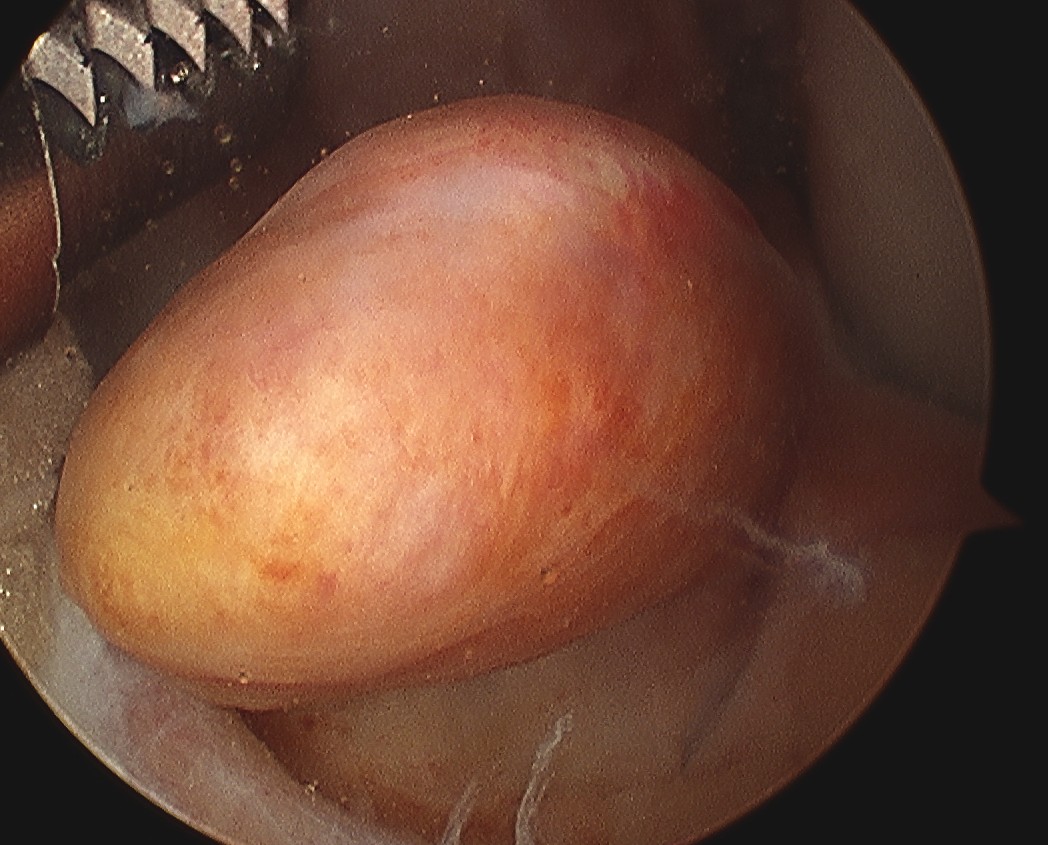

Assess and manage mensicus as appropriate

- assess and manage chondral lesions as appropriate

Debride ACL

Debride stump back to PCL fibres (preserve synovium over PCL)

- can leave some stump to identify tibial tunnel and provide vascularisation

- clean lateral wall

- remove periosteum with curette, chondrotome and electrocautery

- identify resident's ridge and posterior wall clearly